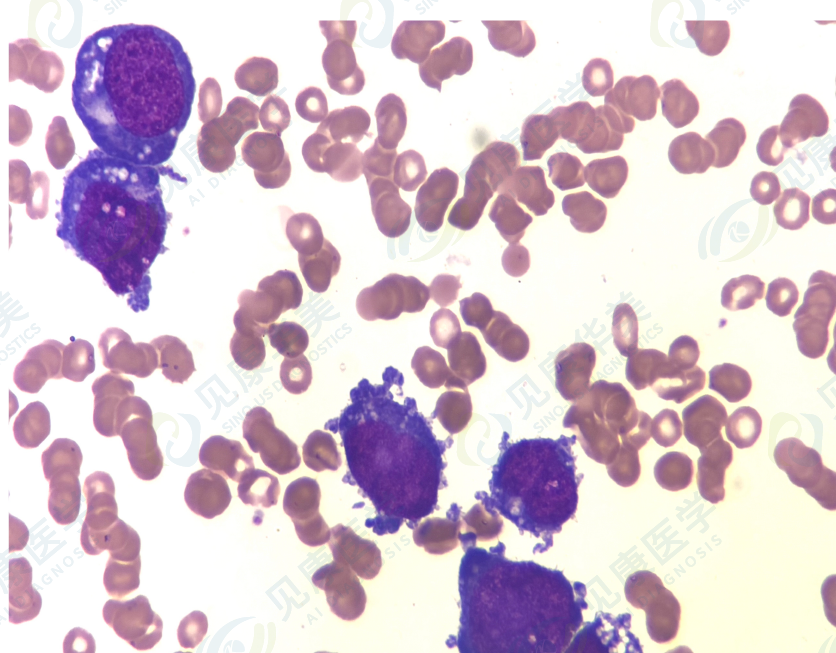

骨髓涂片中该类异常细胞约80%。

骨髓涂片

骨髓形态

AML-M6